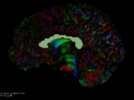

Seeding label map

Output tractography

Seed tractography from a Diffusion Tensor Image (DTI) within a region defined by a label map.